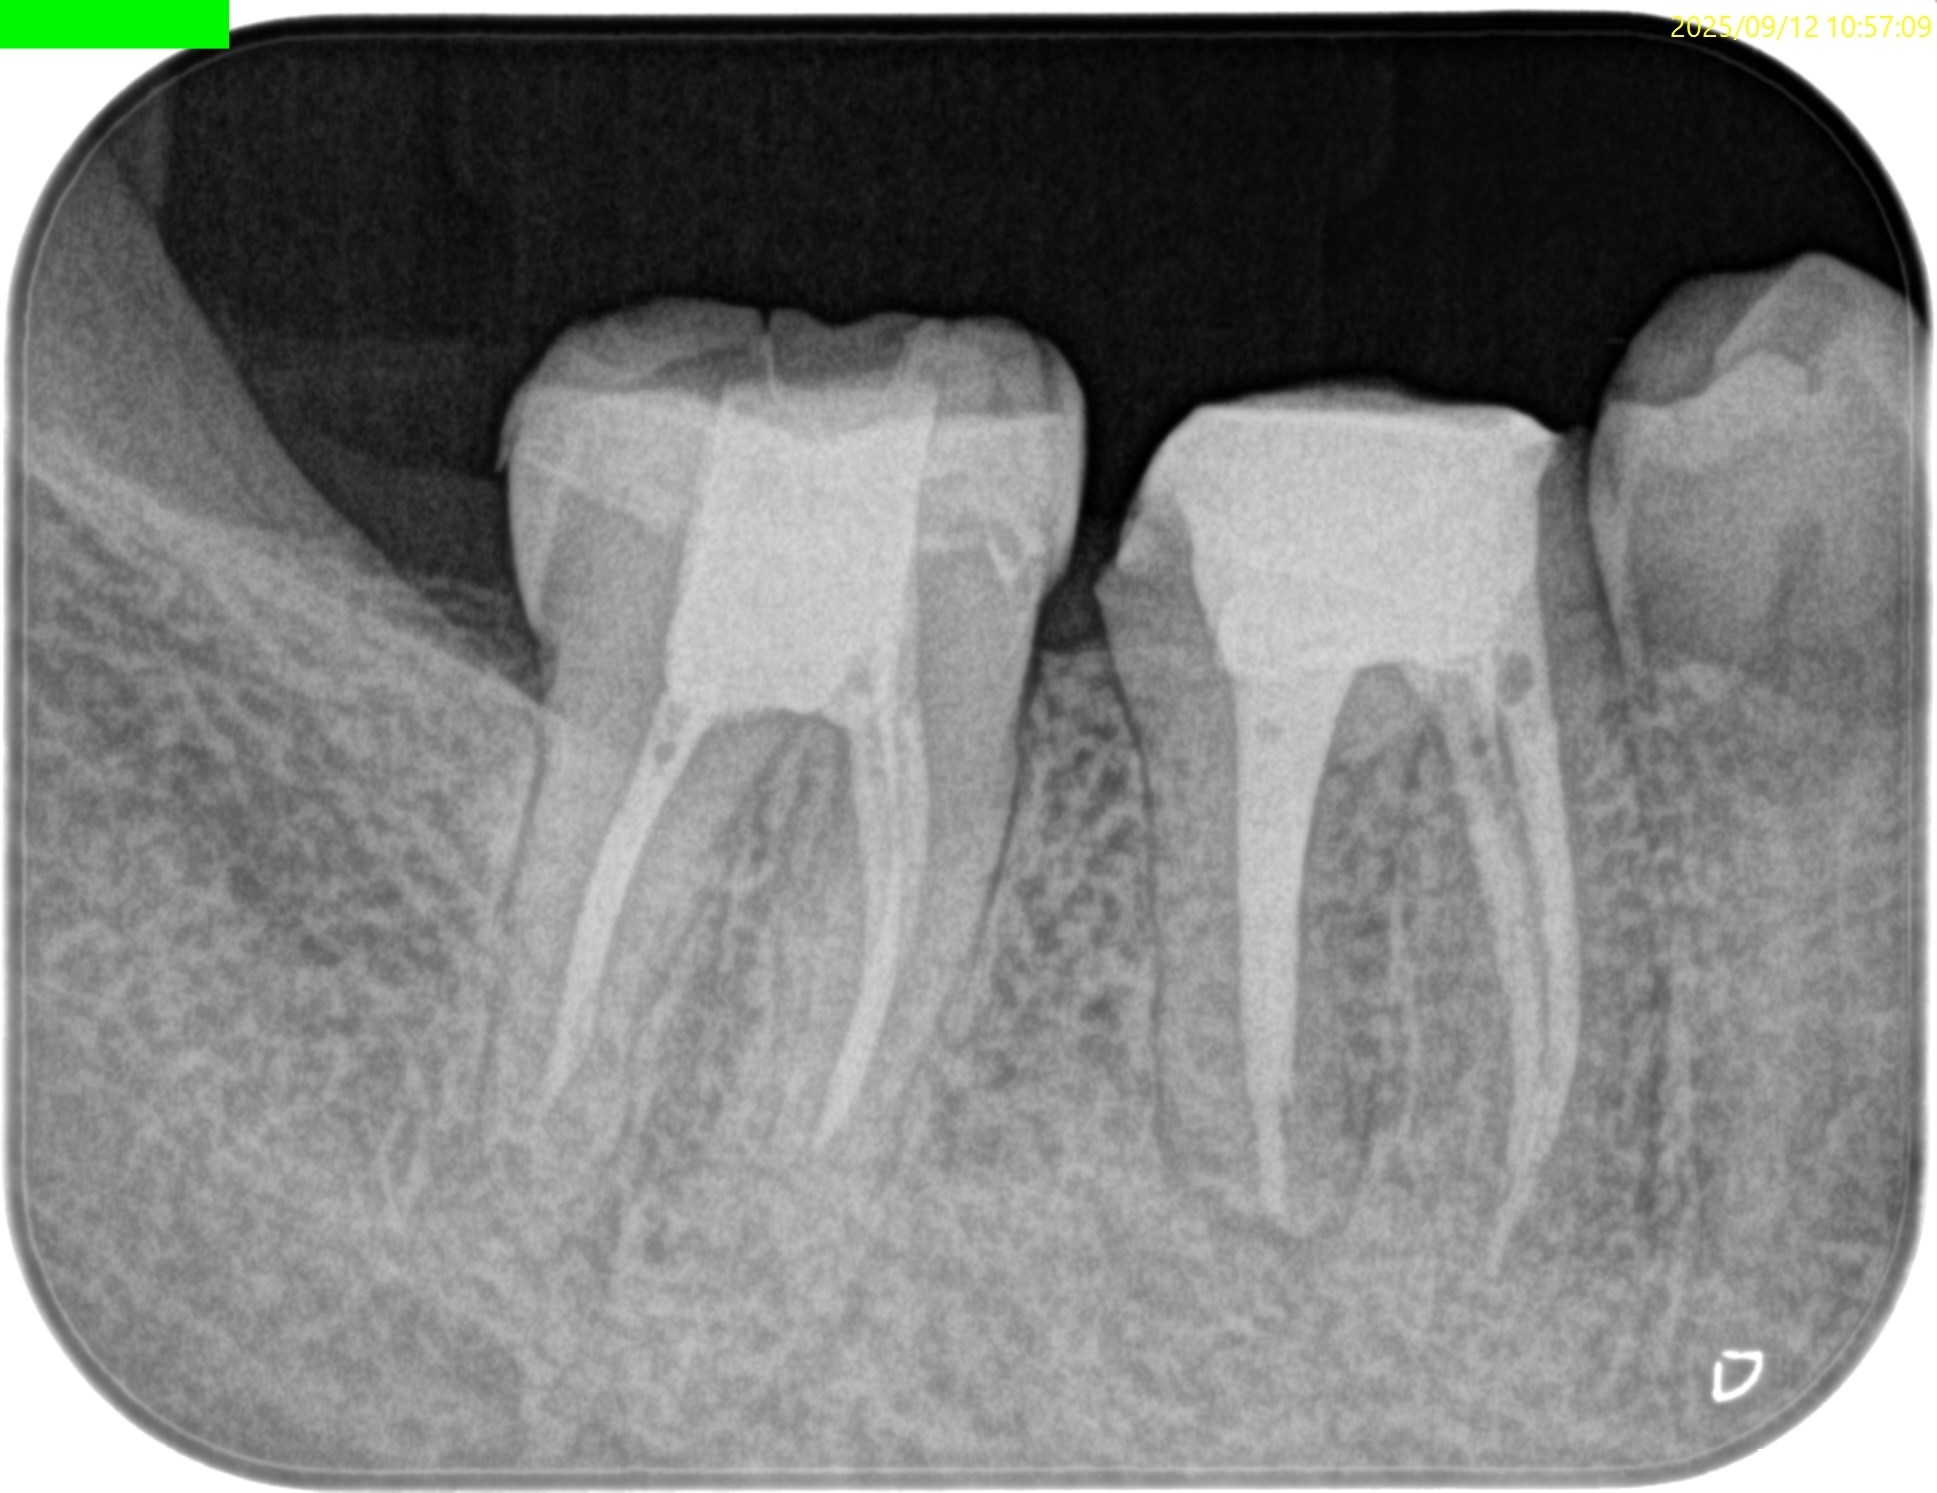

#31 RCT+Core build up(2025.9.12)

根充してPA, CBCTを撮影した。

MB

ML

D

問題はないだろう。